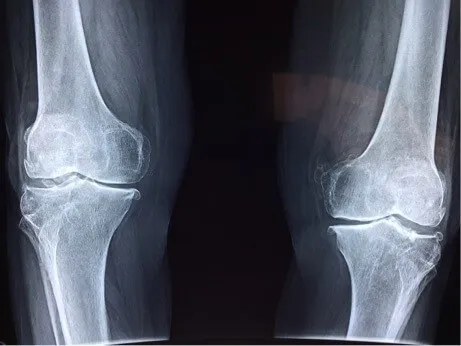

Thousands of people every year in the UK suffer from ongoing arthritic knee pain and don’t do anything about it thinking that it’s just old age and that surgery is the only way to improve symptoms.

Multiple studies in recent years have shown how correctly designed custom foot orthotics can alter function throughout the lower limb thus reducing the pathological effect osteoarthritis has on the inside compartment of the knee.